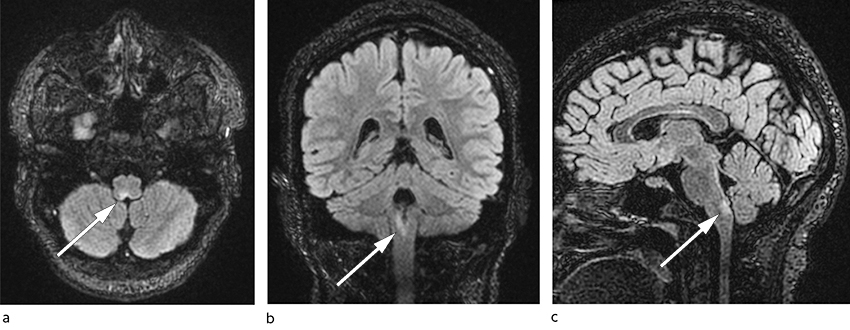

Four days after discharge, the woman was readmitted because of an exacerbation of the problems. The first two days after her discharge she had managed to ingest some food and drink, but then she again experienced acute nausea and vomiting immediately after eating. Clinical biochemical tests were largely unchanged or normalised compared with her first admission: sodium 141 mmol/L, potassium 3.9 mmol/L and slight thrombocytosis 452 × 109/L, but otherwise normal values, including CRP < 1 mg/L, Hb 14.0 g/dL, leukocytes 7.7 × 109/L, ALT 34 U/L, ALP 71 U/L and bilirubin 6 µmol/L. Thirty days after symptom onset a head MRI was performed on suspicion of a central nervous cause of the nausea. A signal change was detected in the medulla oblongata, measuring 4 mm in the axial plane and 11 mm in the craniocaudal direction (Figure 1). It was hyperintense on T2-weighted images, hypointense on T1-weighted images, and had a weak high signal on diffusion-weighted images. The lesion did not enhance with contrast. There were no other pathological signal changes.

In light of the MRI scan, a tentative radiological diagnosis was either subacute phase infarction or demyelinating lesion. The lesion was perceived as the cause of the patient's persistent nausea, vomiting and hiccups, and she was transferred to a hospital with a neurology department. At a clinical neurological examination on admission, 31 days after symptom onset, she was conscious and oriented, and findings on examination of cranial nerves, motility, sensibility and coordination were normal. Her deep tendon reflexes were symmetrically weak. Her gait was normal, and Romberg's test was negative. A secondary examination of the MRI images after her transfer did not rule out a demyelinating disease, and this, coupled with the clinical picture, gave rise to suspicion of neuromyelitis optica spectrum disorder, NMOSD, presenting as so-called area postrema syndrome.

Thirty-five days after symptom onset, treatment with high-dose methylprednisolone was started: 1 g intravenously once a day for five days. Two days after the start of treatment, the nausea was substantially improved, the hiccups gone, and the woman was able to start eating and drinking without vomiting. She was discharged at the end of the methylprednisolone therapy, and subsequent treatment with prednisolone 60 mg per day was tapered over a period of 14 days. A week after finishing the prednisolone therapy, she started prophylactic treatment with rituximab, with an initial dose of 1 g and plans for a future maintenance dose of 500 mg every six months, as the untreated condition carries a risk of new inflammatory central nervous system lesions. At follow-up three months after starting treatment, she had made a full clinical recovery. A follow-up MRI showed a reduction in the size and signal intensity of the lesion.